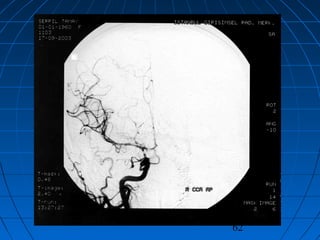

 DÖ: 59 yaşında erkek hastaDÖ: 59 yaşında erkek hasta

 GKS 14 (WFNS grade 2)GKS 14 (WFNS grade 2)

 Fisher grade IVFisher grade IV

64

CERRAHİCERRAHİ

 Sol pterional trans-sylvian yaklaşımSol pterional trans-sylvian yaklaşım

 AcomA Anevrizması kliplendiAcomA Anevrizması kliplendi